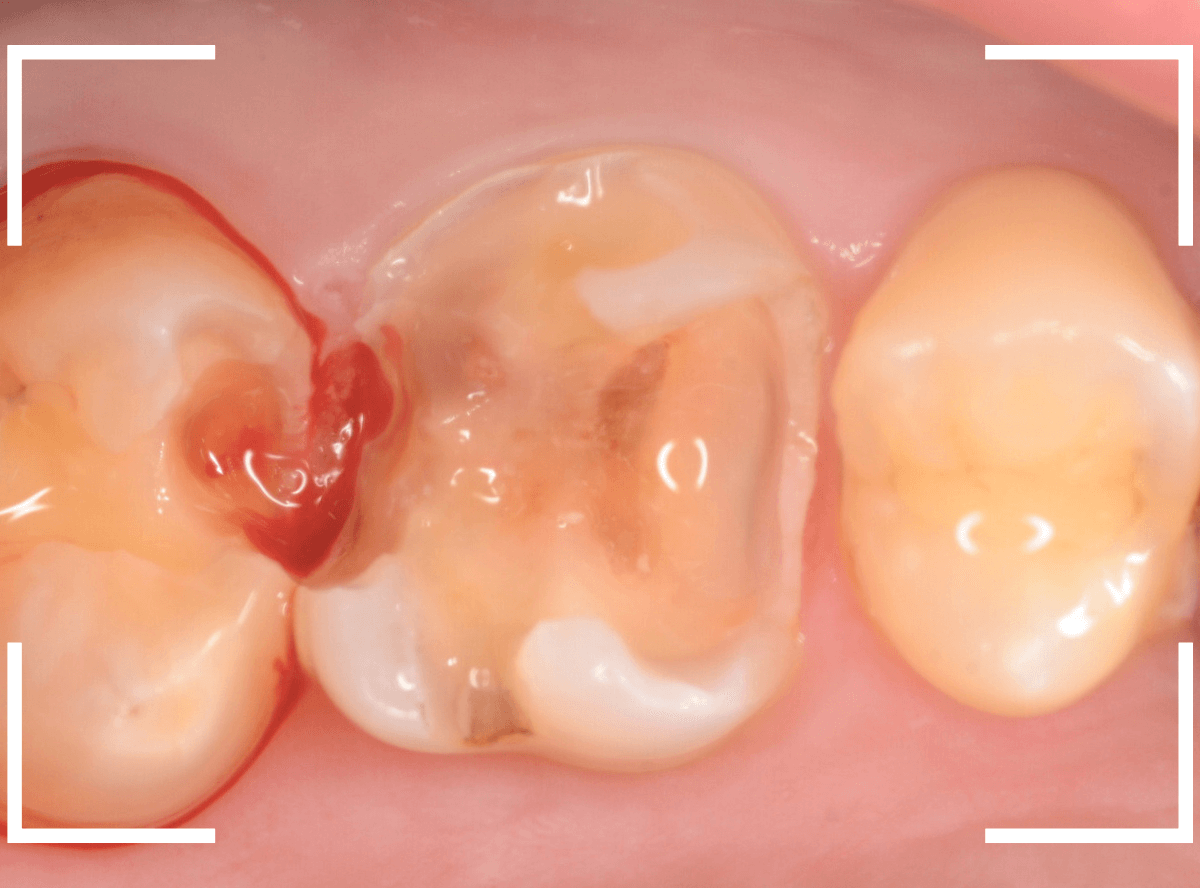

今回は、歯が欠けたという事で来院された患者さんです。

つめものの中で虫歯が大きく進行してしまい、何かの拍子に歯が欠けてしまった状態です(左側)。

右隣の歯もつめものが劣化して中に虫歯が進行しているのが見えます。

早速、虫歯の治療を開始すると、想定通り虫歯で歯の中はボロボロになっています。

虫歯を取りきったところで、歯の神経が部分的に露出し、出血が見られました(露髄)。

かなり厳しい状況で、どうするか悩むところでしたが・・・。

幸い、神経からの出血も少なく、神経が露出している範囲も小さかったため、神経を残せる可能性に賭けて、神経を保存する処置をしました。